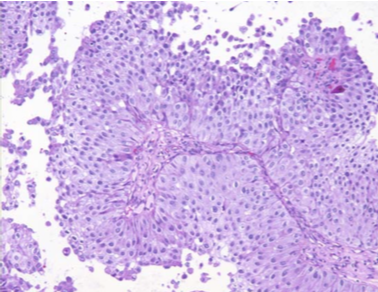

![]() |

| Carcinoma Urotelial de Bajo Grado. Muestra obtenida mediante lavado vesical. Las células neoplásicas exhiben incremento en el ratio núcleo citoplasma. Los núcleos son más hipercrómicos. |